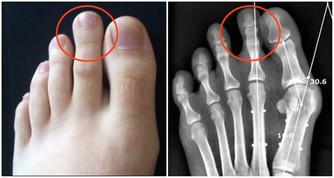

關節處出現“異響”,要警惕是這種疾病找上門!

關節響可能是疾病徵兆

如果開始出現這樣的情況,一定要警惕,就可能是疾病的徵兆。

當人的年齡增大後,關節潤滑液會越來越少,潤滑度不夠,關節必定會出現磨損,這時候就會出現關節炎、骨刺、骨質疏鬆等疾病。

嚴重的甚至會導致骨關節壞死,這種屬於病理性關節響,一般伴隨著疼痛、活動受限,或者關節突然卡住。